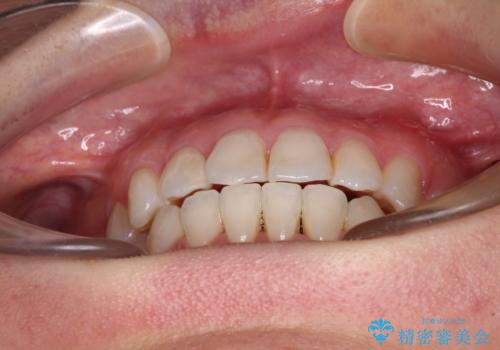

長年気にしていた前歯 インビザラインで目立たず改善

- ワイヤーではない矯正治療があると聞いたとのことで来院された患者様です。

長年前歯のデコボコを気にしていたもののワイヤー矯正に抵抗があり躊躇していたそうですが、インビザラインなら治療してみたいとのことで相談にいらっしゃいました。

インビザライン適用の歯列であったため、歯と歯の間を削るIPRを用いて改善することとしました。

下顎前歯の叢生が顕著な場合、歯列改善後に歯と歯と歯肉の間にブラックトライアングルという隙間ができてしまいます。

軽減することはできますが、完全に解決することは矯正治療のみでは不可能なため、リスクとして事前に周知しておく必要があります。